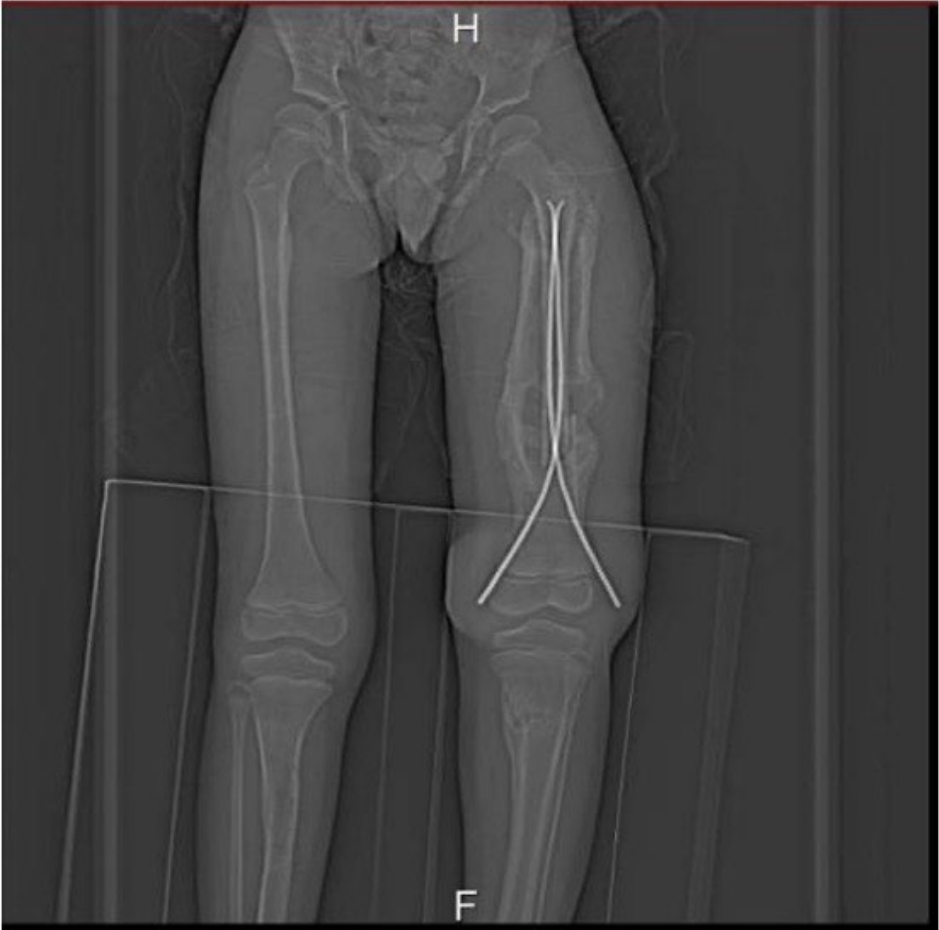

Patients with congenital insensitivity to pain and anhidrosis (CIPA) exhibit an inability to perceive pain, recurrent fractures, self-mutilation, and impaired thermoregulation, which lead to severe complications and high morbidity. Children with CIPA often sustain multiple unnoticed fractures that may be mistaken for child abuse because of the presence of fractures at different stages of healing. If unrecognized or inadequately managed, these injuries can cause permanent damage. We report the case of a 9-year-old boy who presented with recurrent fractures, chronic osteomyelitis, heterotrophic ossification, and gangrene. This case underscores the need for heightened awareness among healthcare providers regarding the clinical manifestations and management challenges of CIPA. It also emphasizes the importance of early diagnosis, meticulous follow-up, and a multidisciplinary approach to optimize outcomes and prevent severe complications in affected children.